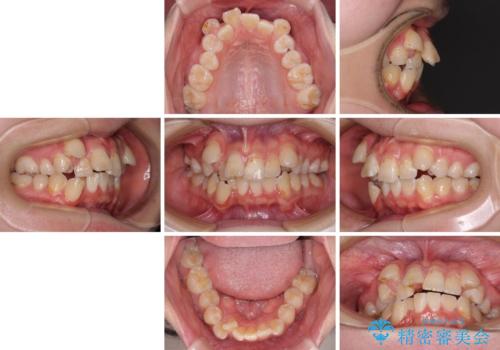

- 八重歯や埋伏している奥歯など、多くの難しい問題を抱えている患者様です。

重度叢生のため、大臼歯をしっかりと咬合させるために、下顎は左右第二小臼歯を、上顎は前歯部の叢生を解消するために左右第一小臼歯を抜歯し、口元の突出感を改善するために、上顎大臼歯が前方に移動しないようにするために、補助装置による架強固定を行うこととしました。

叢生は思ったよりも早期に改善されましたが、舌の突出癖による上下前歯の非接触が全く改善されず、2年間ほど治療期間が延びる結果となってしまいました。